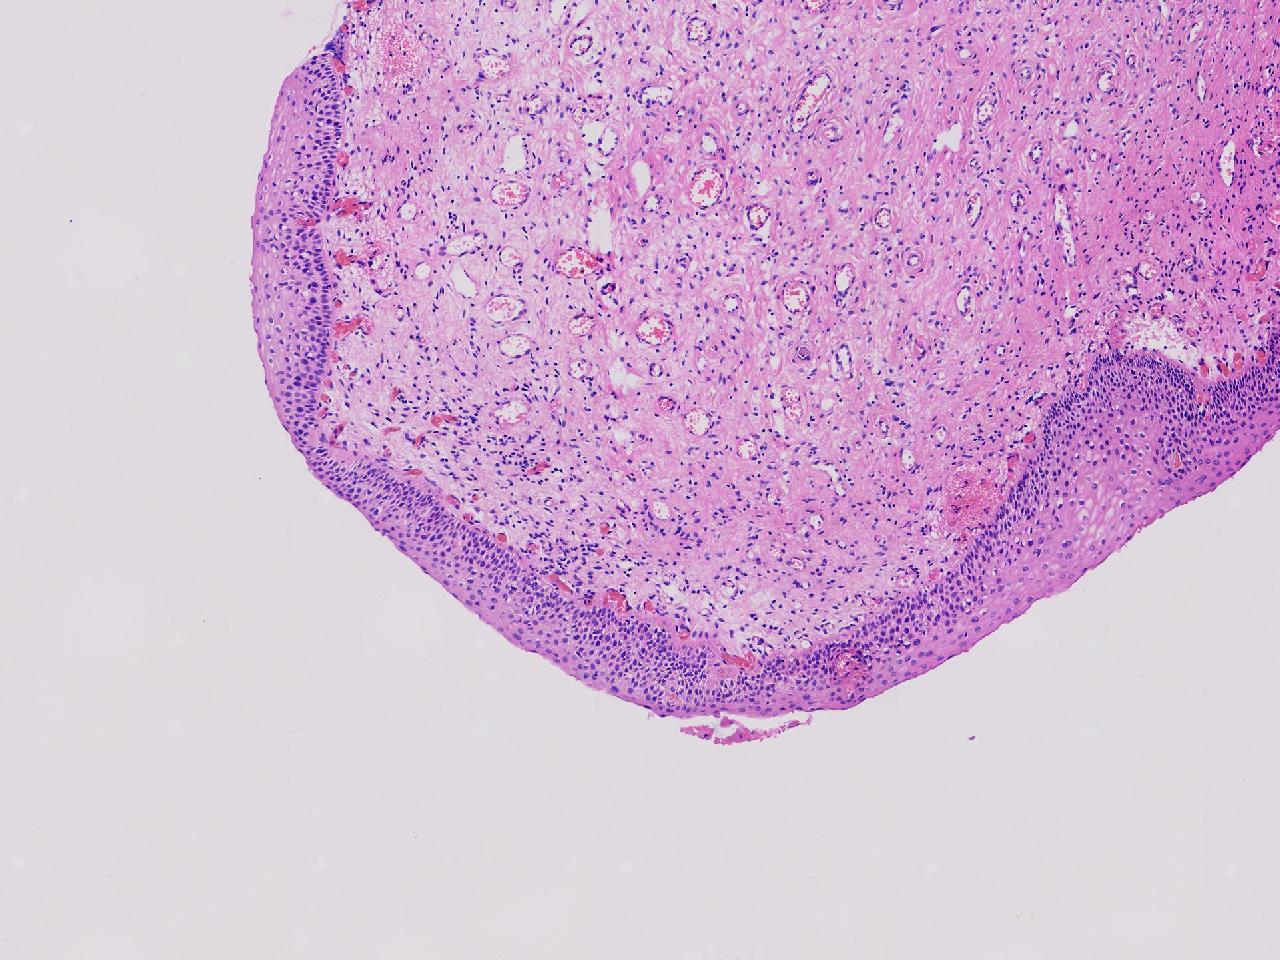

CIN1级? CIN2级?

性别年龄61岁临床诊断

一般病史女,61岁,宫颈活检,,HPV6+ 52+

标本名称宫颈活检

大体所见灰白色不整形软组织1块,直径0.3厘米。

CIN2倒是不够,图3有几个像挖空细胞,HPV有阳,勉强可以考虑小灶LSIL。

• zhuang xia nan:  是的。  2级肯定不够,有挖空细胞,小灶1级。    谢谢老师指点。

CIN1.